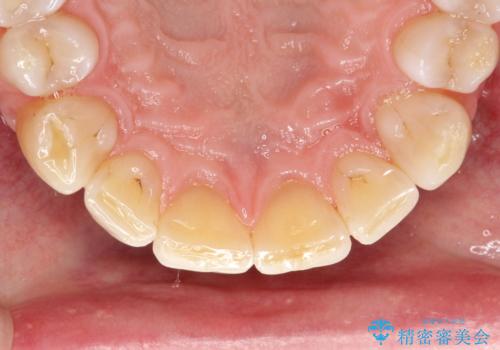

- 歯と歯の間の歯石が気になるとのことで来院されました。PMTC30分コースを行いました。プラークコントロールも悪かったため、歯ブラシ指導も行いました。